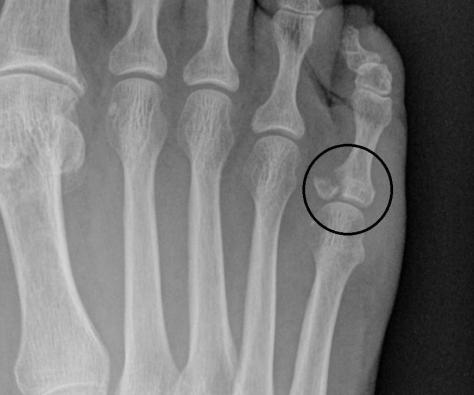

You don’t have to be a radiologist to see what is wrong with this picture.  I broke the knobby end of the toe bone at the joint.  The Urgent Care Dr. suggested I call a Podiatrist.